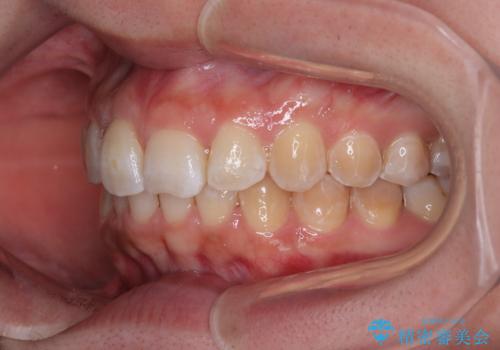

前歯のデコボコをインビザライン矯正で綺麗に改善

- 上下前歯のデコボコを気にして来院された患者様です。

全体的に叢生は軽度であったため、インビザラインにて矯正治療を行うこととしました。

舌の突出癖改善がうまくいかず、途中で舌小帯の切除を行いました。

気になる段差を納得いくまで改善させたため、治療期間は長くなりましたが、綺麗な仕上がりとなりました。